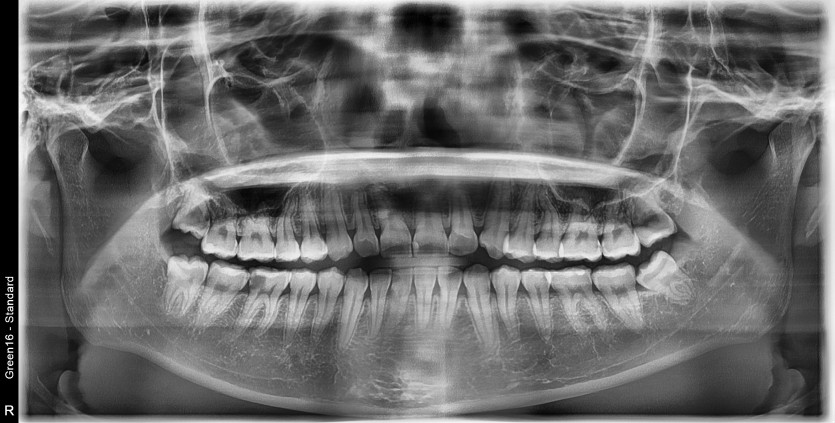

#38,48 사랑니 발치

구강 외과 전문의가 당일 발치했습니다.